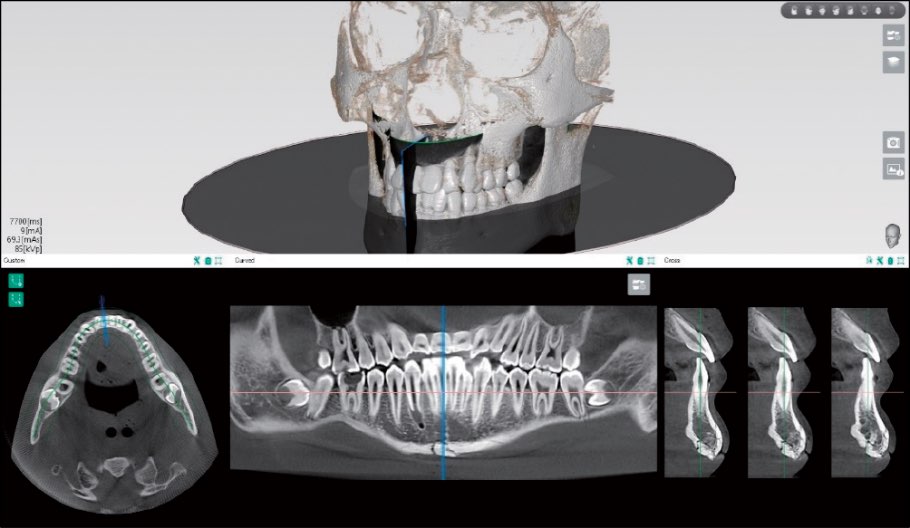

Curved MPR

パノラマ断層カーブを自由に設定し、再構成した断層画像とクロスセクション画像を得ることができます。